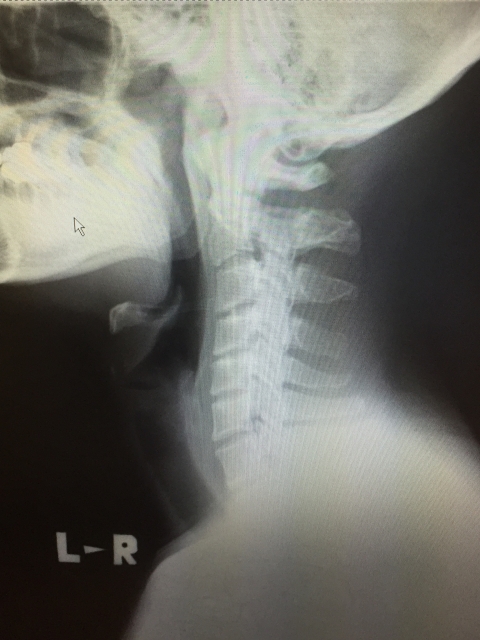

・首/肩回りのストレッチ

このストレッチは最近よく言われる「スマホ首(ストレートネック)」にも効果があるので、現場に入った日でも休みの日でもしたほうがいいかもしれませんね・・・(@_@)